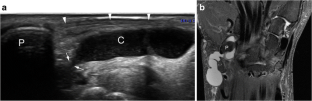

Fig. 1